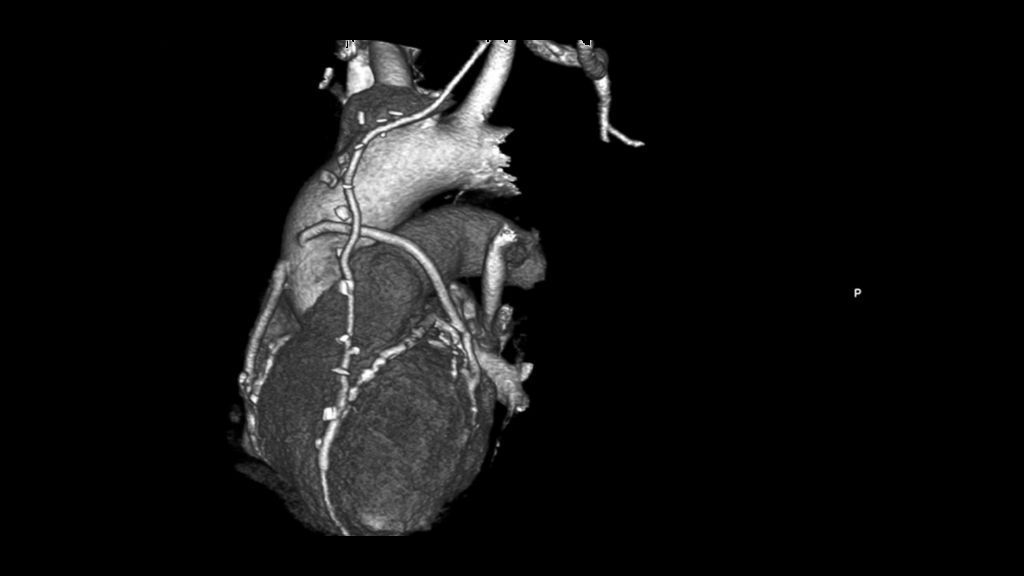

В Казахстане успешно применяется мультиспиральная КТ коронарных артерий

- 3 Февраля 2023

- 138